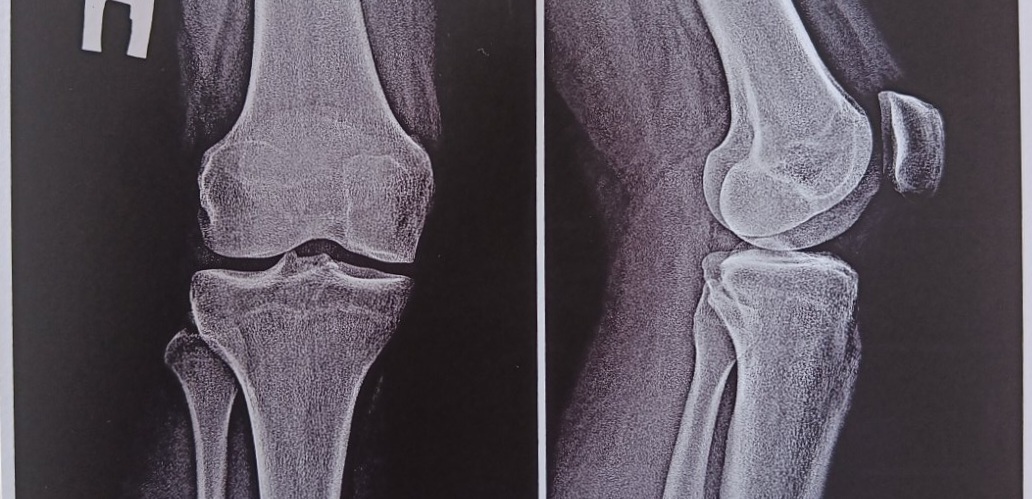

Травм не получала, громкий груст в колене при приседании, не болит. Что может такое быть?